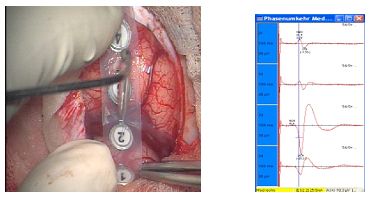

Phasenumkehr zur Differenzierung zwischen sensiblen und motorischen Hinrnarealen

Stimulation von Hirngewebe mit Ableitung von Muskelpotentialen, die im entsprechenden Gebiet repräsentiert werden.